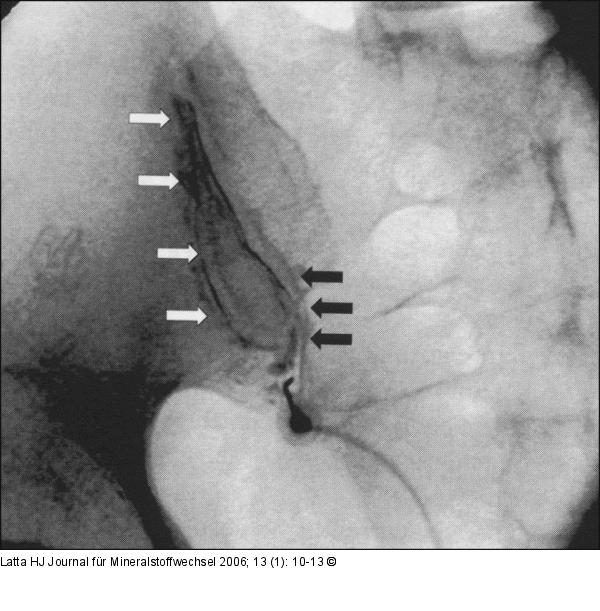

Abbildung 3a-b: Ileosakralgelenk Intraartikuläre Darstellung des linken Ileosakralgelenkes mit KM in zwei Ebenen. |

Abbildung 3b

Abbildung 3a-b: Ileosakralgelenk

Intraartikuläre Darstellung des linken Ileosakralgelenkes mit KM in zwei Ebenen. |